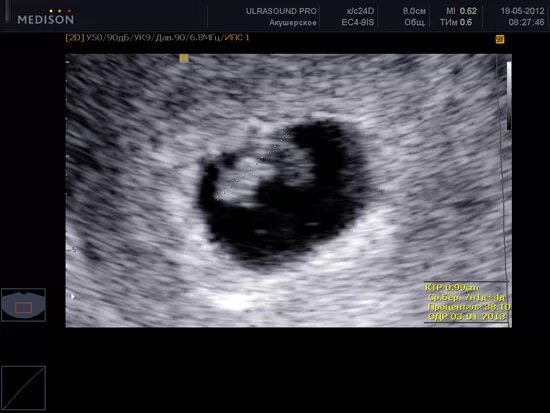

На какой недели можно увидеть плод